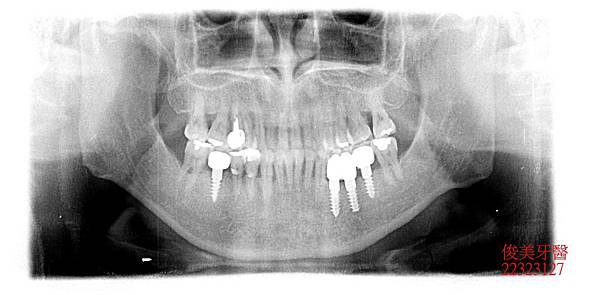

患者為男性,年約46歲,於門診時表示,牙齒有牙周病,想要將牙齒修復,經資料搜集後, 找到我們診所,希望可以做全口性整修;經醫師檢查後發現:患者因有多顆缺牙未做,日積 月累,牙齒造成傾倒,咬合跑掉導致前牙受力過重,牙周狀況不佳,因此為患者設計療程並 詳細說明,患者接受了。

缺牙區皆在後牙咀嚼重力區,因此皆以植牙做修復,以支持整個咬合力量,減輕前牙的受力。